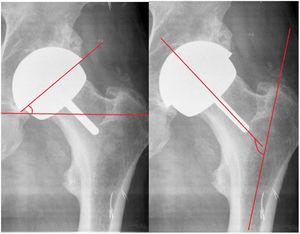

Material y métodosEstudio retrospectivo de cohortes en pacientes intervenidos en nuestro centro con prótesis total de recubrimiento con modelo Durom y su variante MMC Cup en el período de tiempo del 2005 al 2013 con un seguimiento de 84 a 176 meses, con una media de 121 meses. Se realiza estudio demográfico, diagnóstico, índice de masa corporal, complicaciones, reintervenciones y supervivencia del implante. Valoración funcional según la escala de Merle Postel D’Aubigne y Harris Hip Score, valoración radiológica con el sistema Pacs, evaluando: posición acetabular y del componente femoral en proyecciones frontal y axial (fig. 2), radiolucencias en zonas de Lee y Charnley del cotilo; radiolucencias en la zona del vástago según el método de Pollard et al.4, estrechamiento del cuello según la escala de Spencer et al.5 a los 3 meses (fig. 3) y variación offset horizontal. Se utilizó la cotación de Engh para la osteointegración del cotilo (unión, unión fibrosa estable, no unión) y las calcificaciones periarticulares según la cotación de Brooker. Se midieron los niveles de cromo y cobalto en sangre de forma anual en un laboratorio validado para la población general. Se realiza, a su vez, un estudio de supervivencia y complicaciones en la cohorte de pacientes en los que se aplican los criterios de la FDA para la indicación de este tipo de implante: varones activos con edades inferiores a 60 años y cabezas femorales superiores a 48mm6–8.

El ángulo acetabular medio obtenido era de 38,42±8,05 y el femoral de 143,54±8,2°, ratio offset previo y postoperatorio de 0,94. Se observó estrechamiento del cuello en 7 casos (8,53%) en los 3 primeros meses, manteniéndose estable en el tiempo, y calcificaciones tipo ii en 3 casos (3,65%).